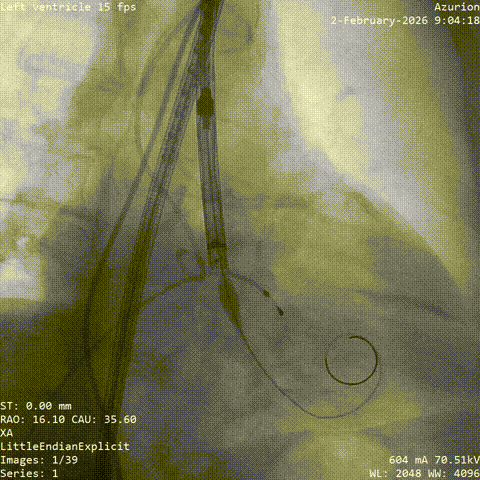

冠脉治疗后一周,张老先生整体状态平稳,进入主动脉瓣置换阶段。团队从股动脉建立通道,将人工瓣膜送至主动脉瓣位置。结合术前评估结果和术中情况,这次手术未进行球囊预扩张,而是直接完成瓣膜释放。

术中,因患者主动脉弓形态较复杂,器械通过一度受阻。团队根据术中情况及时调整策略,最终顺利完成过弓、跨瓣和瓣膜释放。造影及经胸超声显示,瓣膜位置理想、功能良好,左右冠脉血流通畅,未见瓣周漏及血管并发症。

▲根部造影

▲血管扭曲预塑形导丝支撑不足

▲更换导丝后过弓过瓣

▲初始定位

▲左右重合位评估

▲左冠切线位评估

▲最终瓣膜造影

▲入路检查